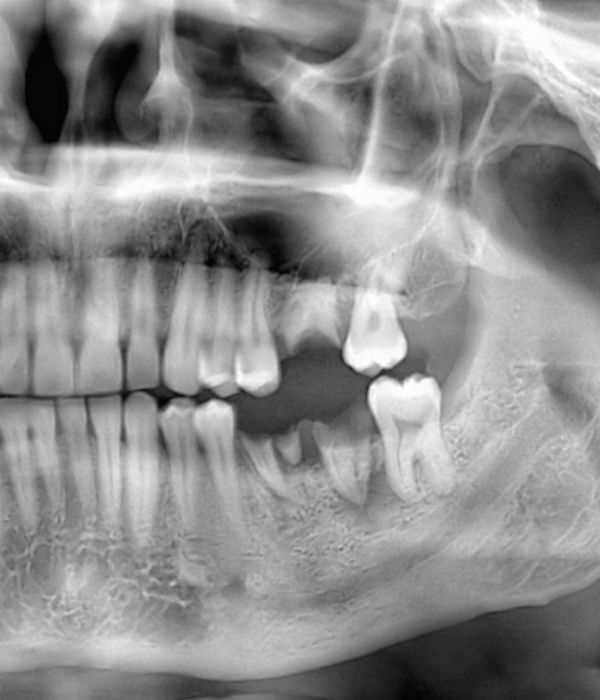

Wisdom Tooth Removal

Dr. Sean Healy and Dr. Diego Hurtado use advanced techniques to minimize discomfort and healing time after wisdom tooth removal. Sedation can ensure your comfort and platelet-rich fibrin, containing growth factors, naturally stimulates the healing process. At a follow-up appointment, one of our surgeons will monitor your recovery.